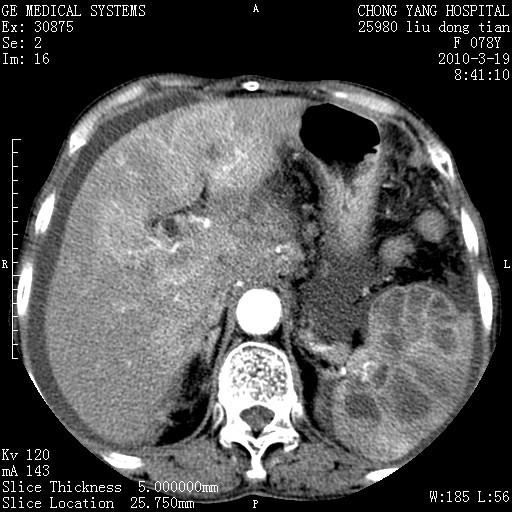

标题: CT25199:F 78Y 腹胀半年 消瘦乏力 [打印本页]

考虑nhl,肝、脾、腹膜腔及腹膜后多发淋巴结受侵,腹水,右肾囊肿,慢性胆囊炎,右侧少量胸腔积液。

胰头有肿块形成,胰头ca伴肝脾、腹膜腹膜后转移

胆囊有软组织影有强化,支持胆囊癌,肝脾、腹膜后淋巴结转移。

nhl的淋巴结多围绕主动脉,而且主动脉会移位,所以不考虑nhl。

分开来讲:肝左叶、尾叶病灶有不均强化像肝癌;

脾脏病灶无强化,像多发囊肿或淋巴管瘤,不除外淋巴瘤(低强化);

肝门、胰腺头、腹膜后多个团块: 淋巴瘤,转移;

脾脏病灶像车轮 莲花,第一感觉还像包虫呢。真想全切出来一个个做病检。

胰头ca伴肝脾、腹膜腹膜后转移!

最后报的胰头癌多发转移,脾脏单独考虑囊肿或淋巴管瘤。